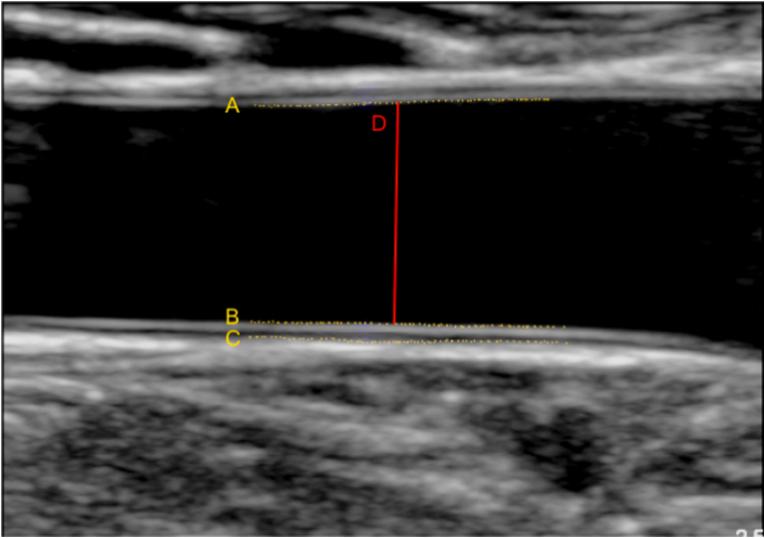

Increased common carotid artery (CCA) intima media thickness (cIMT) is a well-known risk factor for cardiovascular morbidity and mortality. cIMT thickening has been described in patients with repaired aortic coarctation (CoA), but data on mechanism and clinical relevance in this population are scarce. Our aim was to gain mechanistic insights into cIMT thickening of patients with repaired CoA by comparing their wall architecture to patients with coronary artery disease (CAD), other congenital heart diseases (oCHD), and healthy controls.

A total of 310 subjects were included (CoA (n ​= ​58), oCHD (n ​= ​96), CAD (n ​= ​68) and healthy controls (n ​= ​88)). CIMT and lumen diameter (LD) were determined using semiautomated analysis software. Linear regression analyses were performed correcting for relevant covariates. While patients with repaired CoA and CAD both had significantly increased cIMT and cIMT/LD ratios, LD was increased only in CoA patients. Furthermore, patients with repaired CoA had decreased CCA stiffness. CCA characteristics in the oCHD group were not significantly different from controls.

The mechanism of cIMT thickening in patients with repaired CoA may differ from CAD. While there is concentric remodeling in the latter, we see predominant eccentric remodeling in the CoA group, which could be due to increased flow as a result of compliance mismatch at the CoA repair site. We therefore suggest that the prognostic value of cIMT in post-CoA patients should be validated separately prior to using it to guide clinical management in this group.